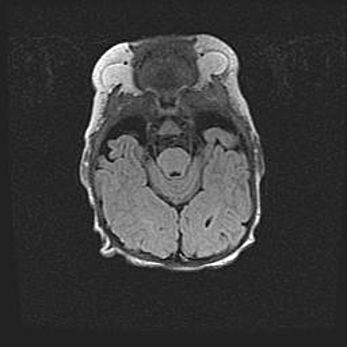

Подострая гематома правой гемисферы мозжечка.

Наружная гидроцефалия.

Возраст: 15 дней

Вес: 3100 г

Пол: женский

Окружность головы: 37 см

Срок гестации: 35-36 недель

При открытой наружной форме гидроцефалии у новорожденных расширяются и переполняются субарахноидные пространства.

Кровоизлияния в мозжечок имеют две клинико-анатомические формы: полушарные гематомы и кровоизлияния в червь.

К появлению этой патологии может привести: повреждения головного мозга, возникающие в результате асфиксии и гипоксии плода при беременности, или травмы во время родов. Редко гематома мозжечка может быть результатом первичной коагулопатии и сосудистой мальформации, диссеминированном внутрисосудистом свертывании, изоиммунной тромбоцитопении.